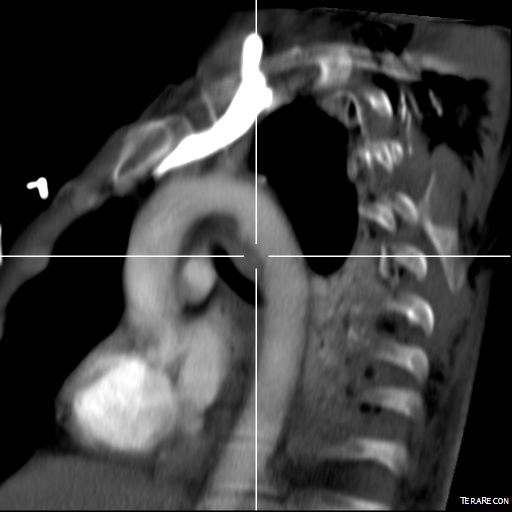

This patient presents with lifestyle limiting claudication and an absent right femoral pulse. ABI is moderately reduced on the right to 0.57, and he had no rest pain. CTA at our clinic revealed an occluded EIA bracketed by severely calcified and nearly occlusive plaque of the common iliac artery (CIA) and common femoral artery (CFA).

The patient was operated on in a hybrid endovascular OR suite. A right groin incision was made to expose the common femoral artery for endarterectomy and left common femoral access was achieved for angiographic access, but also to place a wire across the occlusion into the common femoral artery.

All actions on the external iliac artery plaque are done with an up-and-over wire, allowing for swift action in the instance that arterial perforation or rupture occur. This event is exceedingly rare when the operation is well planned. With this kind of access, an occlusive balloon or repairing stent graft can be rapidly delivered.